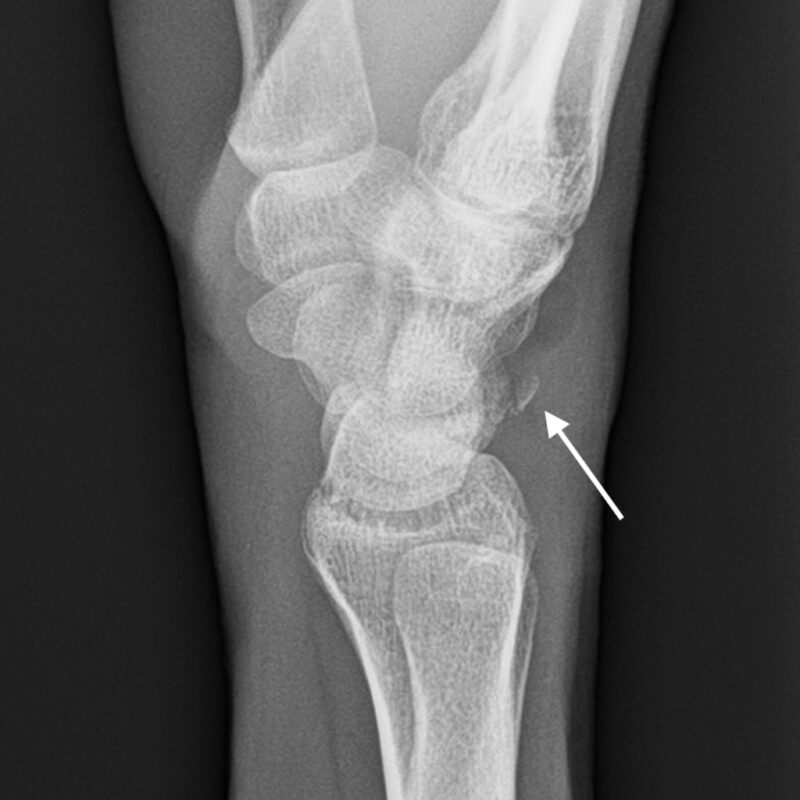

From www.researchgate.net

An AP view radiograph of the right wrist showing collapsed capitate Chip Fracture Definition This usually results from an accident or. Bei chipfrakturen handelt sich um kleinere knöcherne absprengungen (chips) der dorsalen fläche des triquetrums. An avulsion fracture happens when a piece of bone attached to a tendon or ligament gets pulled away from the main part of the bone. An avulsion fracture occurs when a small chunk of bone attached to a tendon. Chip Fracture Definition.